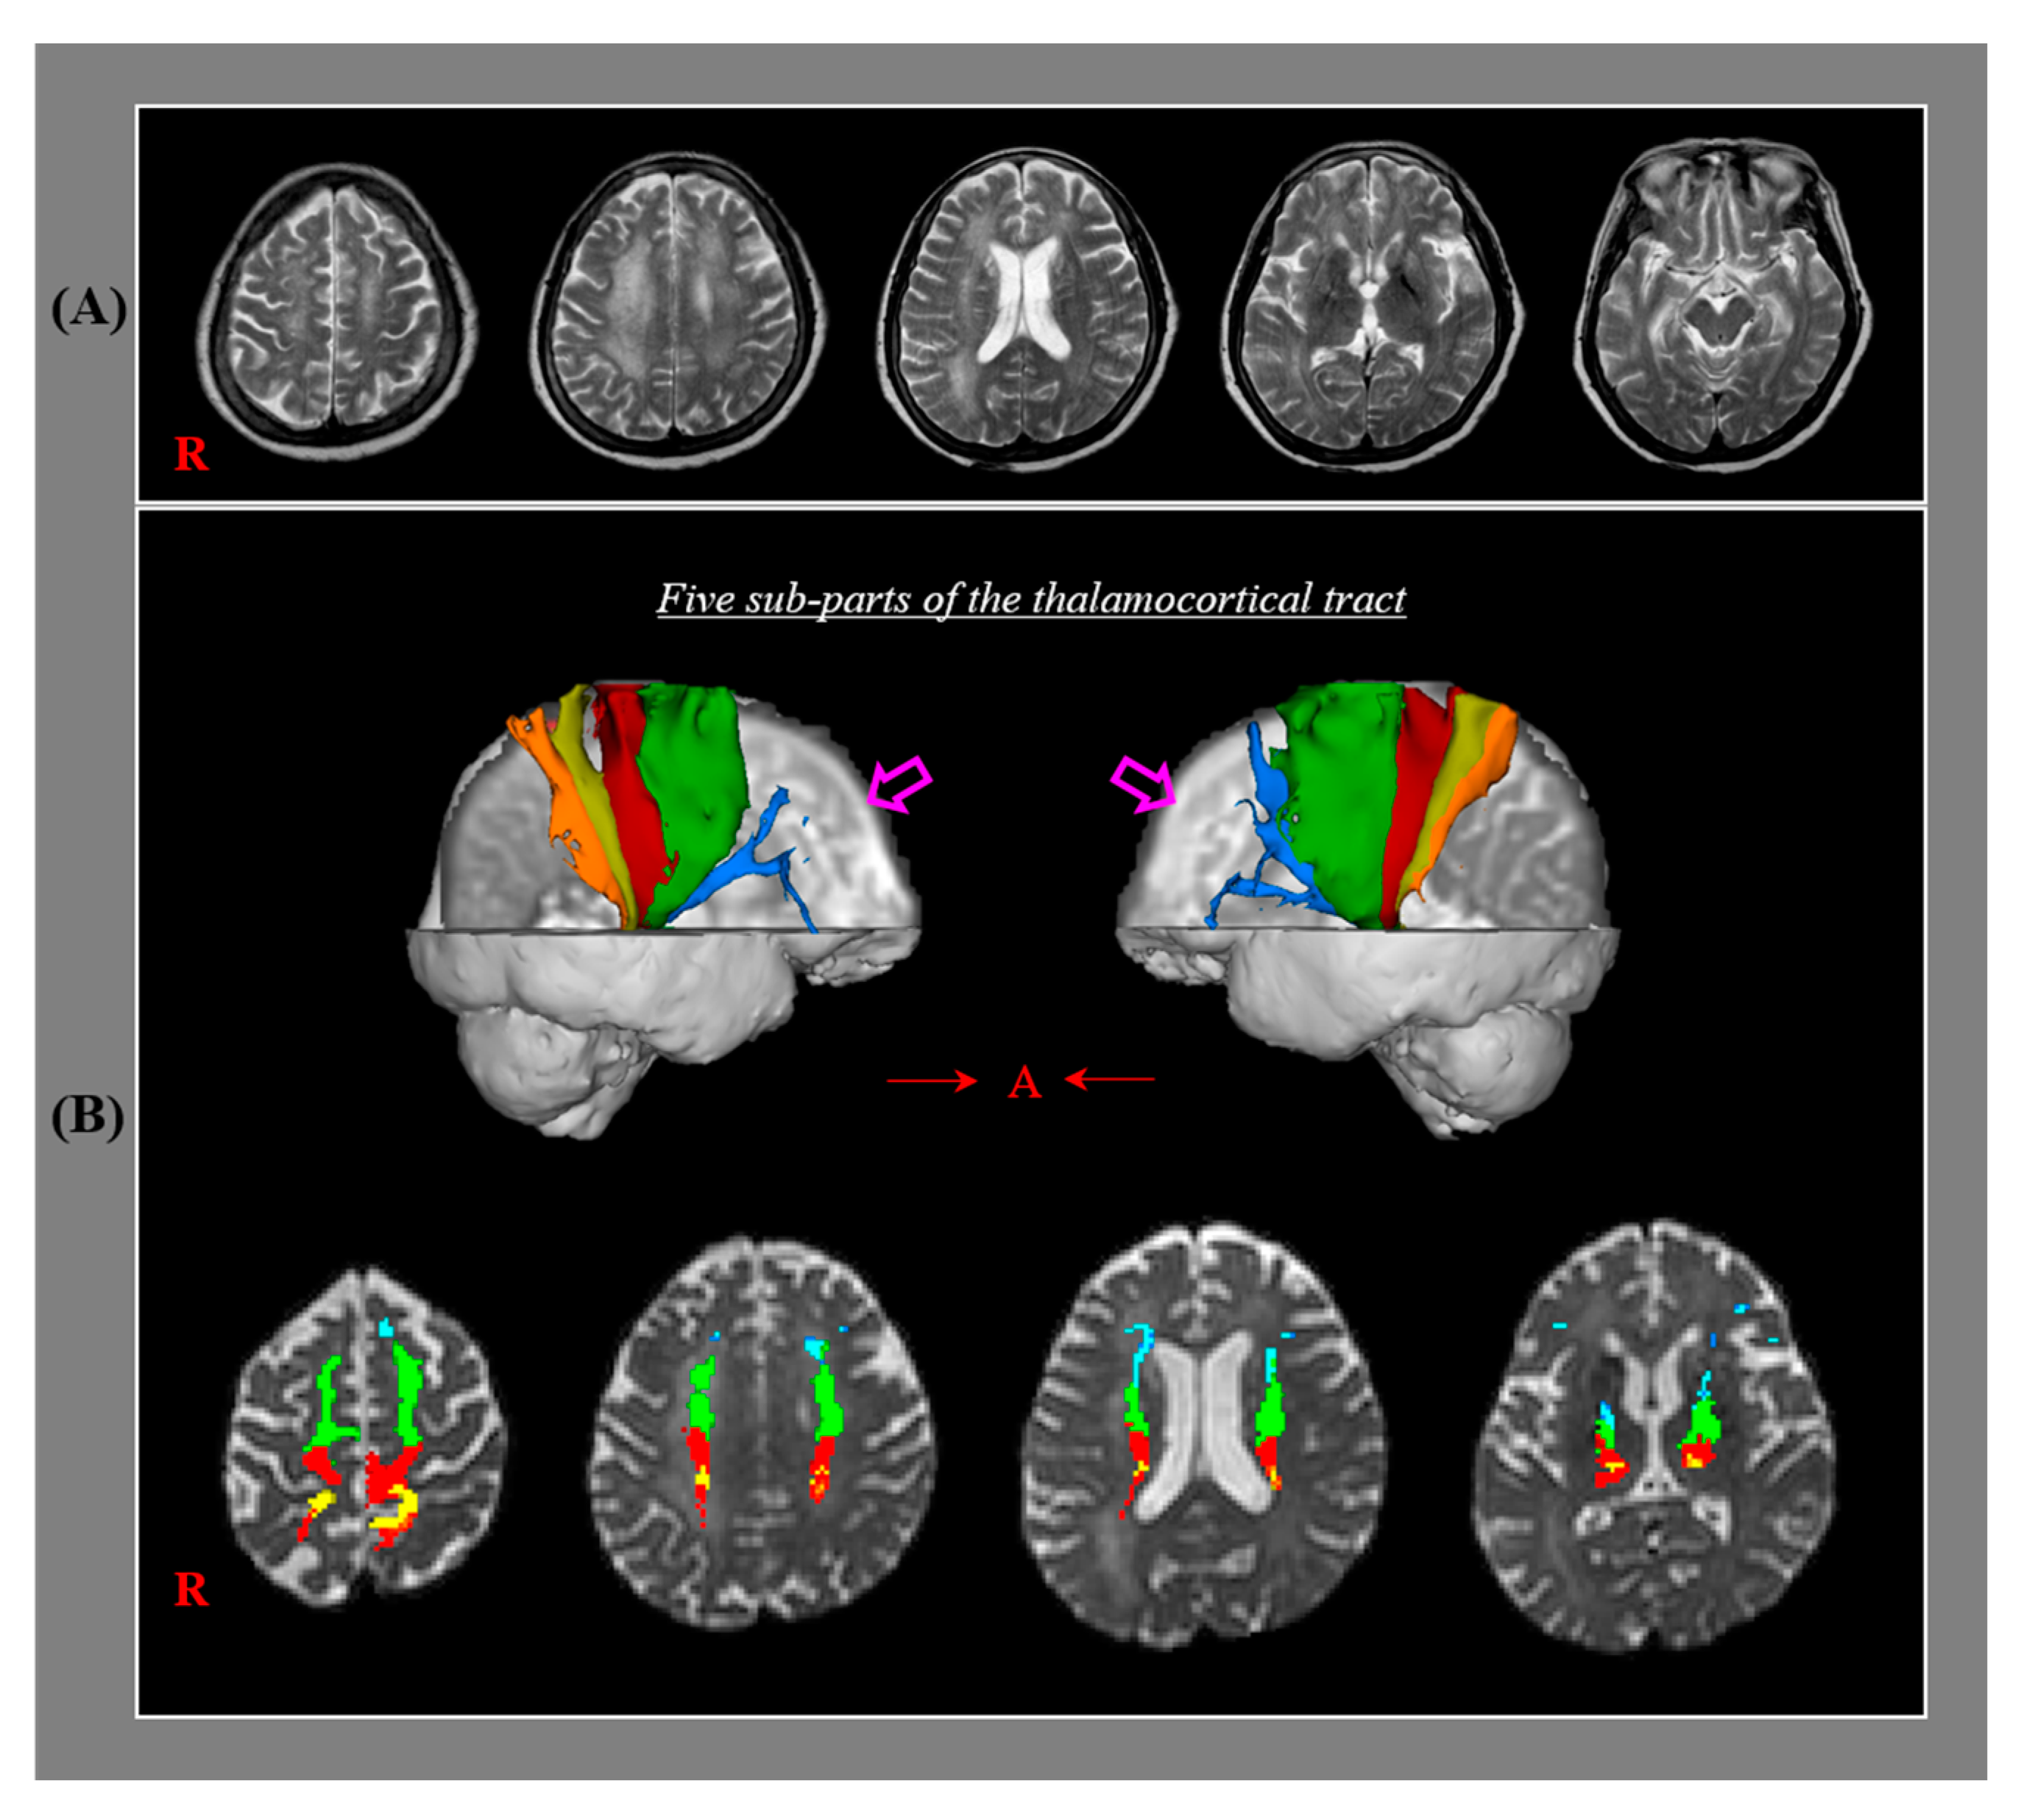

51X8DJl7i5L.jpg_BO30,255,255,。Mobilisation of the Nervous System: 9780443044007: Medicine。Frontiers | The Influence of Neuron-Extrinsic Factors and。Mobilisation of the NERVOUS SYSTEM洋書デイビット・バトラー表紙に細かいスレ傷等、傷み、汚れがあります。【書籍】奇跡を呼ぶ ヒーリングコード。。The Nervous System - An Introduction - Mariska Odendaal。中に書き込みは見当たりませんが、見落としはご了承ください。中古本にご理解の上ご購入ください。Molecular Biology of the Gene (第7版)